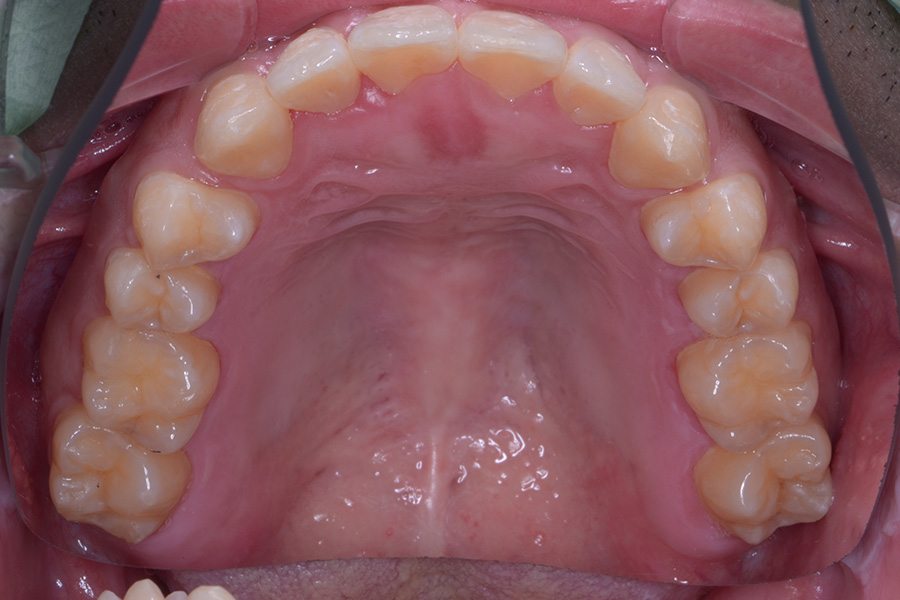

【30代男性】上の真ん中の隙間だけ治したい

• 治療前

• 治療後

主訴 上の真ん中の隙間だけ治したい

期間 7か月

費用 治療費15万(別途調整料)

デンタルローン50回 ¥3400/月

治療内容 上顎ラビアル矯正(表側矯正)

治療に伴うリスク 後戻り